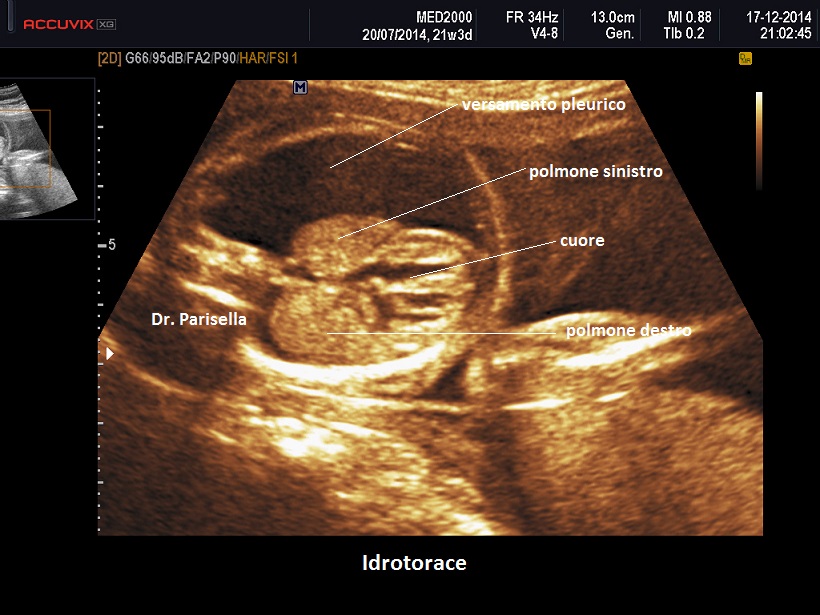

Diagnosi Ecografica

La diagnosi ecografica non offre in genere difficoltà ed è rappresentata da un versamento pleurico monolaterale o bilaterale.

Nelle forme monolaterali si ha shift mediastinico con dislocazione controlaterale del cuore.